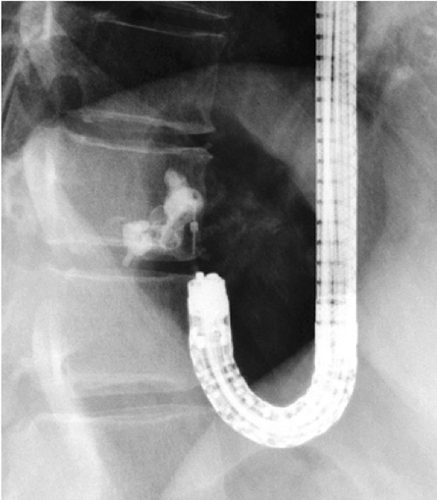

内視鏡的静脈瘤造影(endoscopic varicealography during injection sclerotherapy:EVIS)

内視鏡的硬化療法(EIS)(図[ID0608])のX線透視像。硬化剤が供血路に逆行性に注入されている。

出典

img

1: 著者提供